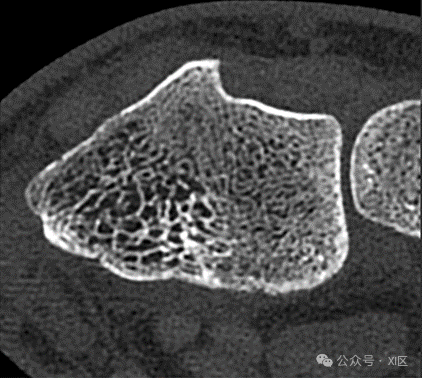

26岁男性,舟骨骨折患者。图像显示腕部在利斯特结节水平(窗宽,1500 HU;窗位,450 HU)。轴位超高分辨率(UHR)能量积分探测器CT图像显示,与下图相比,单个小梁的分辨率较低。该检查使用SOMATOM Force扫描仪(西门子医疗)在120 kV下进行,CTDIvol为14.4 mGy。图像以0.4毫米层厚、卷积核Ur73和512 × 512矩阵大小重建。

光子计数探测器CT图像显示出比上图更高的分辨率的单个小梁(即使两个扫描都是使用UHR模式获得),这是因为减少了部分容积效应和更高的空间分辨率。该检查使用SOMATOM Count Plus扫描仪(西门子医疗)在120 kV下进行,CTDIvol为9.7 mGy。图像以0.4毫米的截面厚度用Br84核和1024 × 1024矩阵大小重建。